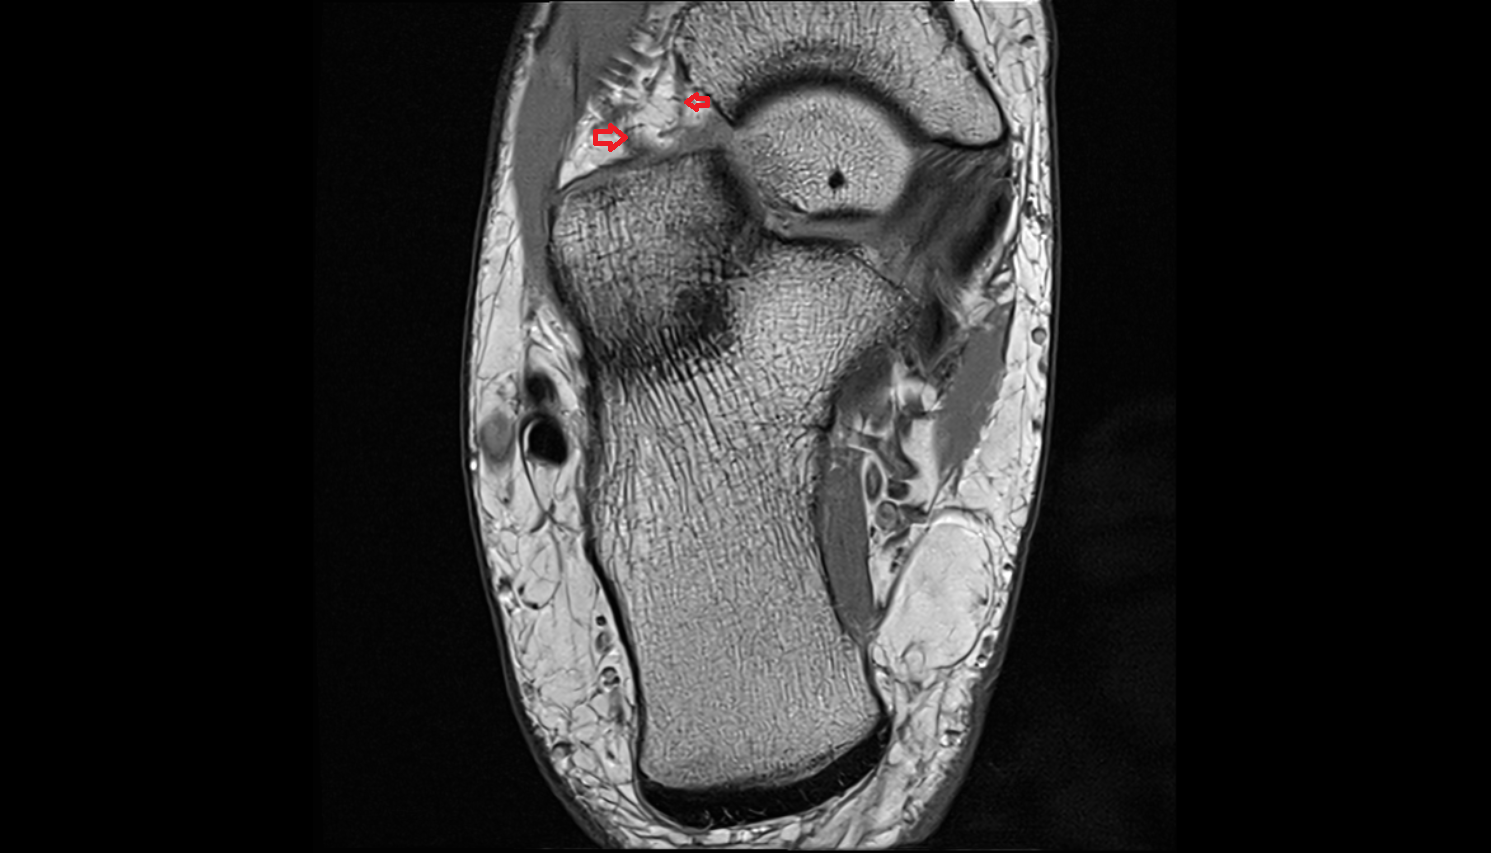

- Temporomandibular joint

- Mandibular condyle

- Mandibular fossa

- Articular disc of temporomandibular joint

- Articular eminence